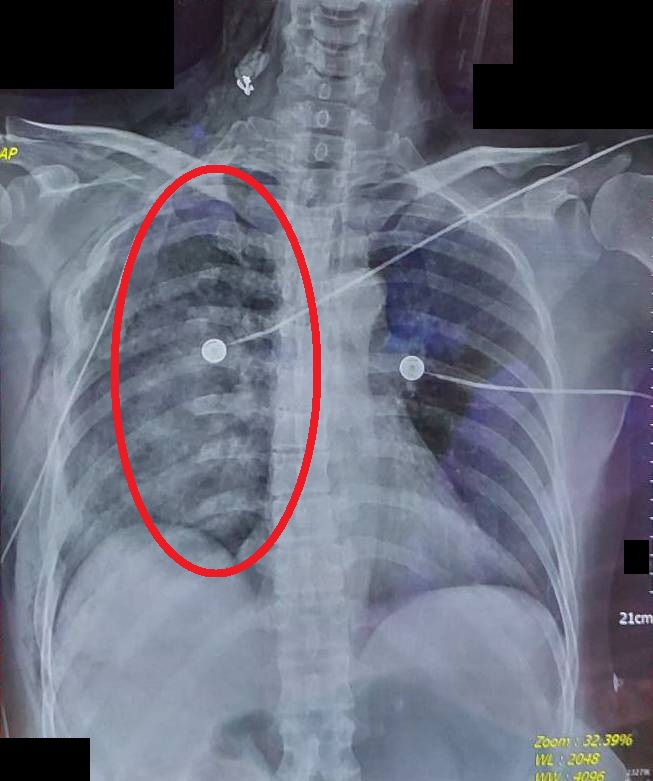

【大紀元2025年04月18日訊】(大紀元記者陳文敏台灣苗栗報導)50歲的賴女士因意外失足跌入深水溝,有呼吸困難、嚴重胸痛的情況,因此緊急送醫。經胸部X光與電腦斷層檢查,發現有多處肋骨骨折,其中部分骨折處產生移位,形成典型的「連枷胸」合併出現肺挫傷與局部塌陷,導致嚴重的呼吸困難。醫療團隊立刻安排微創肋骨骨折固定手術,將骨折的肋骨固定回正確的位置,使胸壁恢復穩定性,改善病人呼吸狀況。

此次案例病人接受微創肋骨骨折固定手術來穩定胸壁,透過鈦合金骨板與螺釘,將骨折的肋骨固定回正確的位置,順利改善呼吸功能。手術後病人的呼吸狀況明顯改善,不再需要高濃度氧氣支持,並逐步接受呼吸復健訓練,術後一週已經能夠下床活動,並在兩週內順利出院。目前門診追蹤顯示,肋骨癒合情況良好,肺部功能也逐漸恢復。